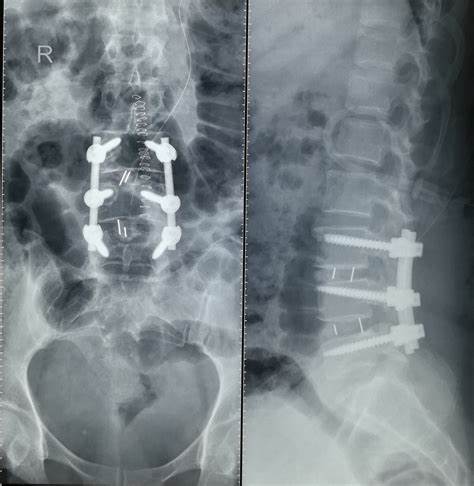

●您的腰椎间盘突出特别的严重 , 辅助检查显示有明显的椎管狭窄 , 并且出现了下肢的萎缩 , 甚至出现了明显的间歇性跛行 , 也就是说行走几百米的距离 , 甚至一、二百米的距离就需要休息 , 否则就疼痛难忍 , 这种情况是一个比较明确的手术适应症 。